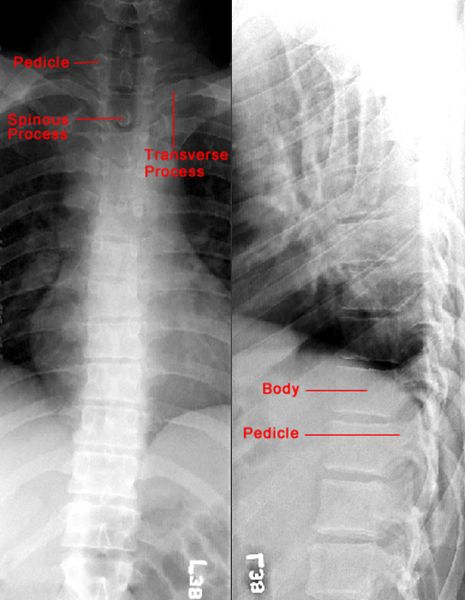

正常胸椎

正常腰椎